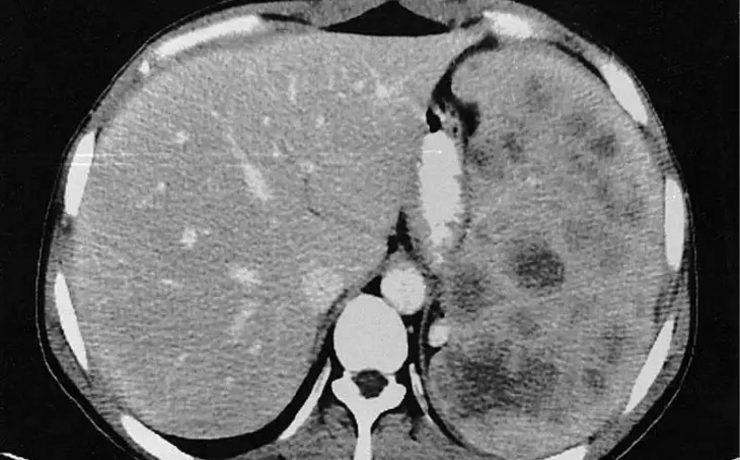

Quiste hidatídico primario de bazo

La hidatidosis es una enfermedad causada por Equinococus granulosus y que afecta principalmente a zonas endémicas donde existe disminución de la higiene, lugares con corrales o animales con problemas intestinales, alimentos donde se consumen vísceras crudos, en lugares urbanos se ha visto este tipo de patología donde abundan los perros